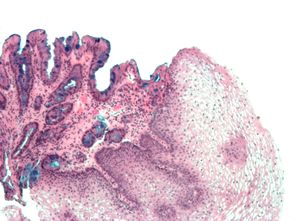

바렛 식도의 진단에는 내시경 검사와 현미경을 통한 조직학적 확인이 모두 필요하다. 특히, 장(腸) 형성이상이라고 불리는 술잔 세포의 존재가 필수적이다.[21]

진단을 내리기 위해서는 육안적(내시경 검사) 및 현미경적 양성 소견이 모두 필요하다. 바렛 식도는 정상적인 편평 세포 상피를 대체하는 하부 식도에 원주 상피의 존재로 특징지어진다. 이는 화생의 예시이다. 분비성 원주 상피는 위액의 침식 작용을 더 잘 견딜 수 있지만, 이러한 화생은 선암종의 위험을 증가시킨다.[15]

바렛 식도 진단에는 내시경 검사를 통한 육안적 소견과 현미경을 이용한 조직학적 소견이 모두 필요하다. 바렛 식도는 하부 식도에서 정상적인 편평 세포 상피가 원주 상피로 대체되는 화생 현상이다. 분비성 원주 상피는 위산에 의한 손상에 더 강하지만, 선암 발생 위험을 높인다.[15]치료에도 불구하고 역류 증상이 오래 지속되는 60세 이상 남성은 선별 내시경 검사를 받는 것이 좋다.[16] 예상 생존 기간이 5년 미만인 경우에는 선별 검사가 권장되지 않는다.[16]

조직학적, 병리학적 정의에 따르면, 바렛 식도는 "식도 내 장상피화생을 동반한 원주상피"로 정의되며, 원주상피화생과 점막근판의 2층화가 특징이다.